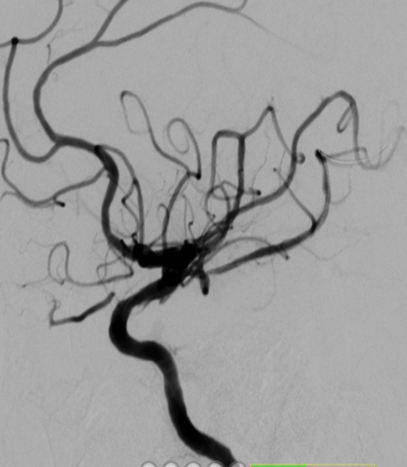

术后影像及检查

影像结论:术后残余狭窄小于 10%。

导丝怎么扩【载药时代 球扩天下】NOVA DES®颅内药物洗脱支架在颈内动脉颅内段重度狭窄中的应用体会二例!_https://www.jmylbn.com_新闻资讯_第30张